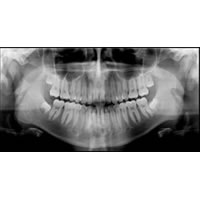

歯科用CTを完備

レントゲンでは見られない骨の内部や神経・血管の位置がわかります。

幅広く治療に応用することができ、正確な審査・診断により、治療の安全性を高めます。